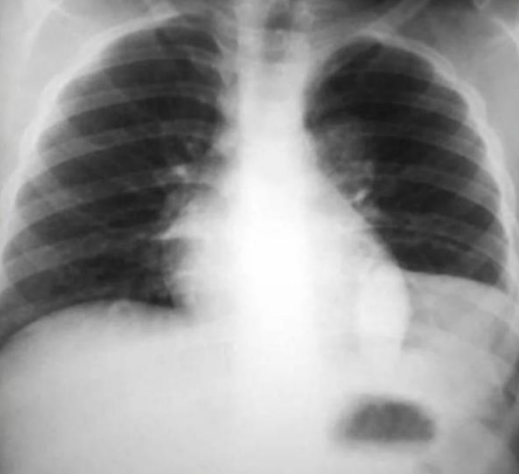

¿Qué distribución tiene la lx?

"Alas de mariposa"

Distribución en "alas de mariposa" se asocia a:

Influenza | O edema pulmonar alveolar